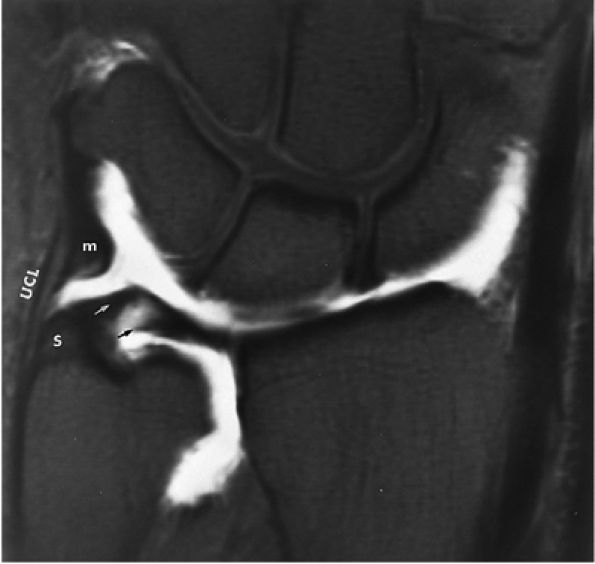

![]() |

FIGURE 10.62 ● Anatomy of the radioscaphocapitate (RSC), radiolunotriquetral (RLT), and radioscapholunate (rsl) ligaments at the level of the distal volar radius (R). T, triquetrum; S, scaphoid. FS T1-weighted arthrogram after radiocarpal injection.

FIGURE 10.64 ● The radiolunotriquetral or long radiolunate ligament. This ligament acts as a volar sling for the lunate. Coronal T1-weighted arthrogram.